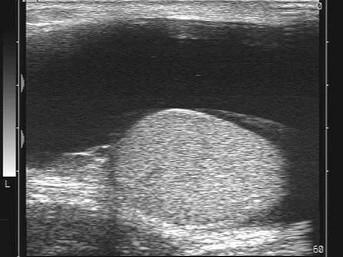

某患者阴囊超声声像图如下,最可能的诊断为?(?)A.睾丸鞘膜积液B.精索鞘膜积液C.阴囊水肿D.附睾囊肿E.交通性鞘摸积液

问题 某患者阴囊超声声像图如下,最可能的诊断为?(?)

选项 A.睾丸鞘膜积液 B.精索鞘膜积液 C.阴囊水肿 D.附睾囊肿 E.交通性鞘摸积液

答案 A